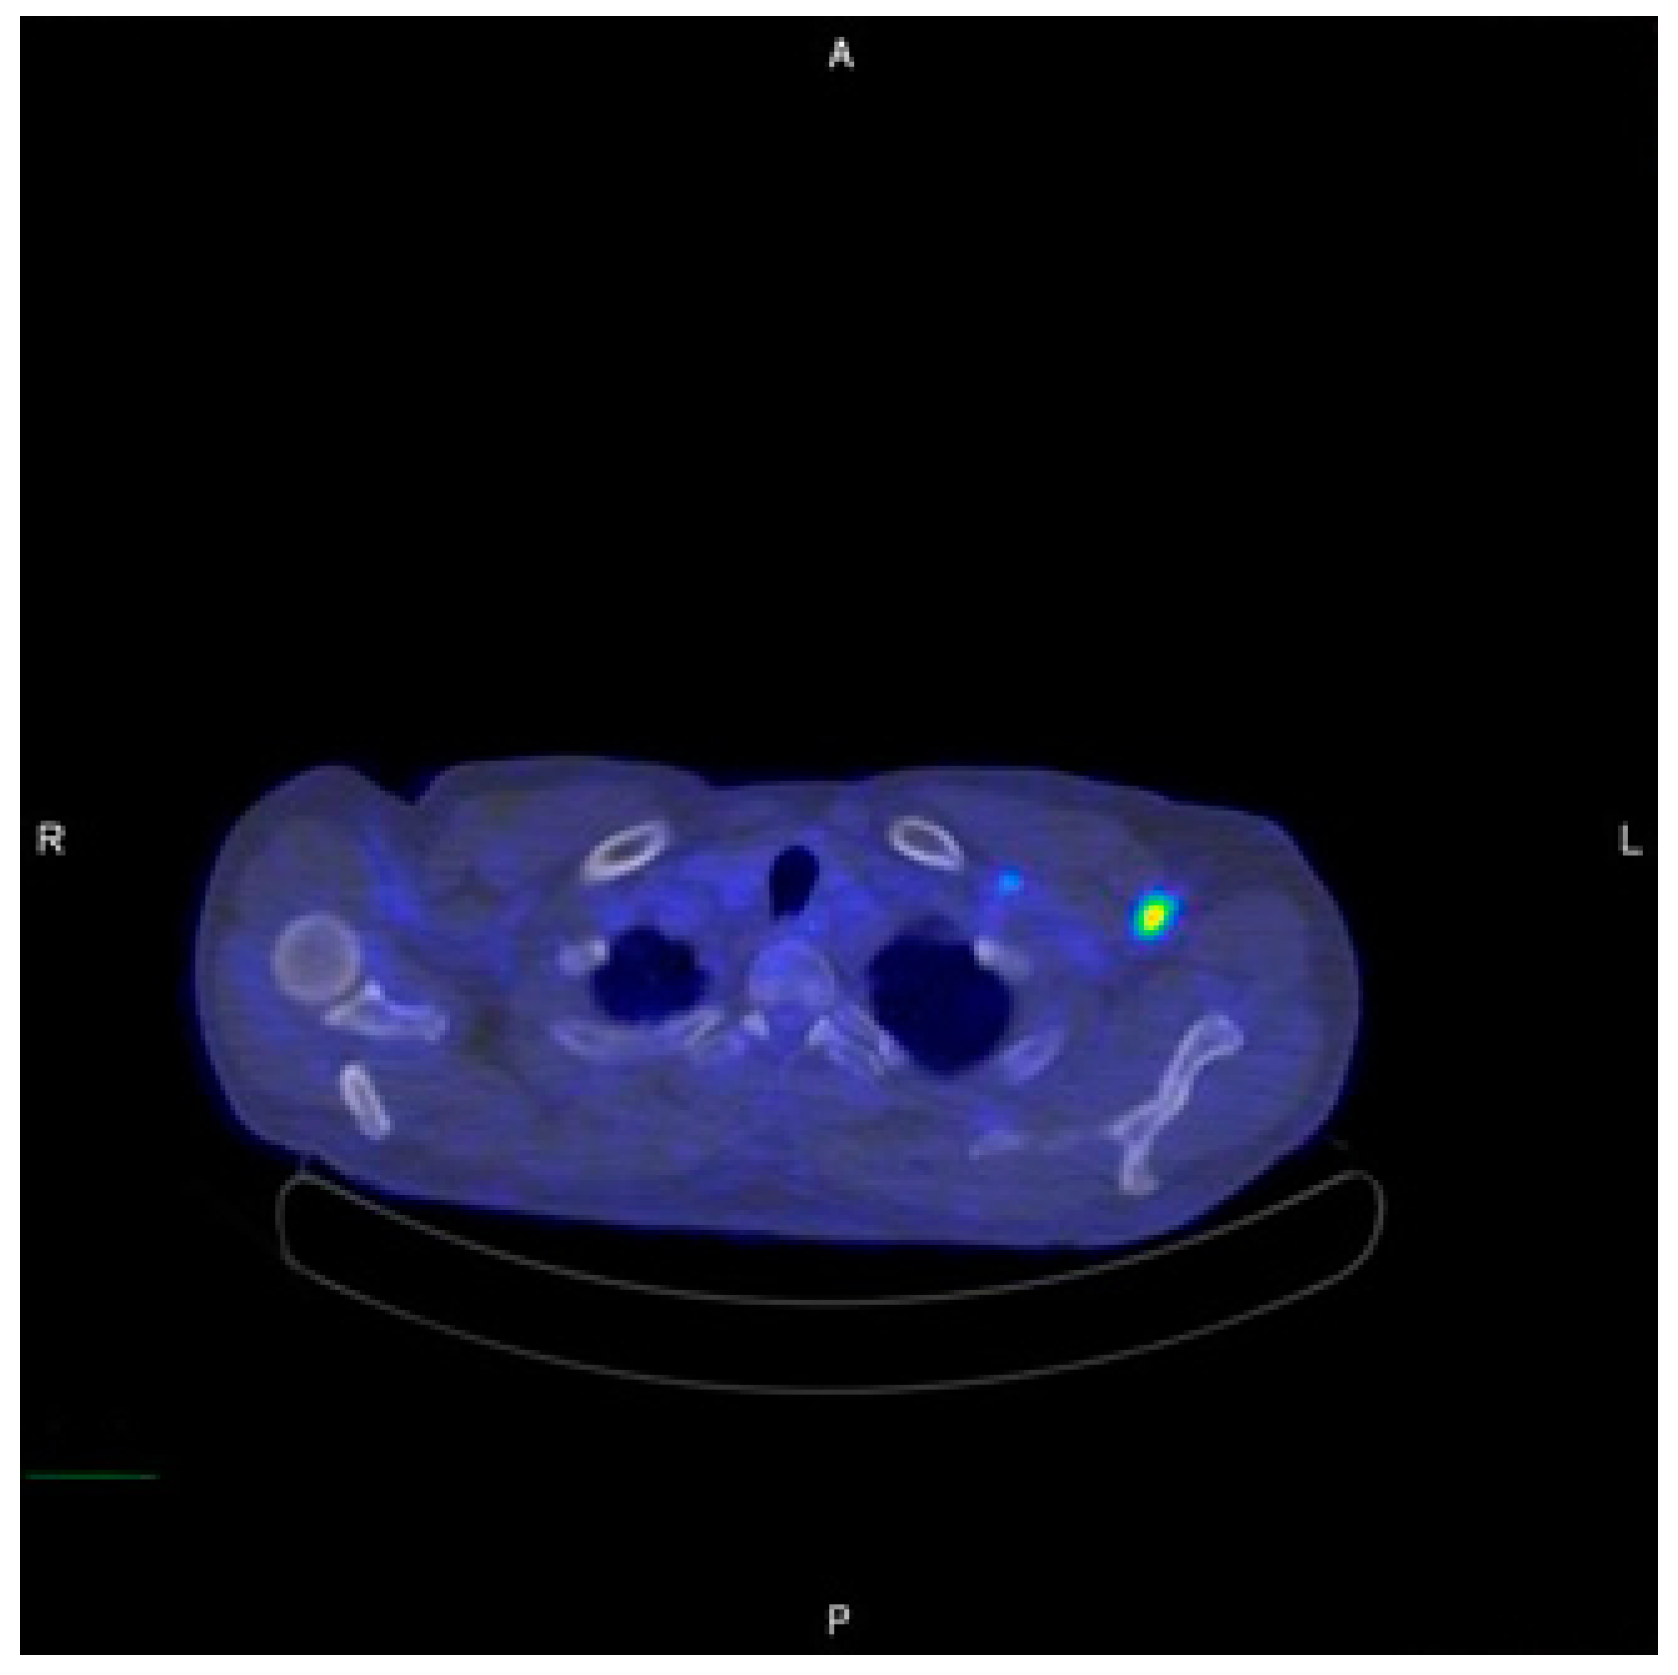

2. Case Report